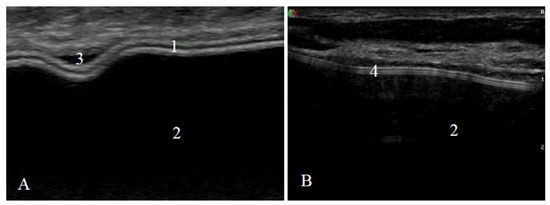

Axillary lymph nodes were assessed as normal (oval shape, smooth cortex, unchanged, clearly visible fat gate) or containing silicone (a sharp upper border and sides, a loss of the lower border due to the “snowstorm” artifact) (Figure 3).

Figure 3. Signs of an axillary lymph node on ultrasound: (A) lymph node with normal appearance (oval shape, smooth cortex, unchanged, clearly visible fat gate) and (B) lymph node with silicone (a sharp upper border and sides and the loss of the lower border due to the “snowstorm” artifact).